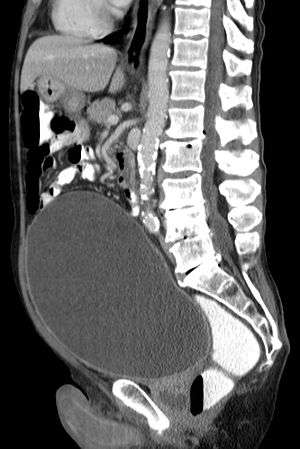

Urinary retention with greatly enlarged bladder at CT.

As seen on axial CT

Analysis of urine flow may aid in establishing the type of micturition (urination) abnormality. Common findings, determined by ultrasound of the bladder, include a slow rate of flow, intermittent flow, and a large amount of urine retained in the bladder after urination. A normal test result should be 20-25 mL/s peak flow rate. A post-void residual urine greater than 50 ml is a significant amount of urine and increases the potential for recurring urinary tract infections. In adults older than 60 years, 50-100 ml of residual urine may remain after each voiding because of the decreased contractility of the detrusor muscle. In chronic retention, ultrasound of the bladder may show massive increase in bladder capacity (normal capacity is 400-600 ml).